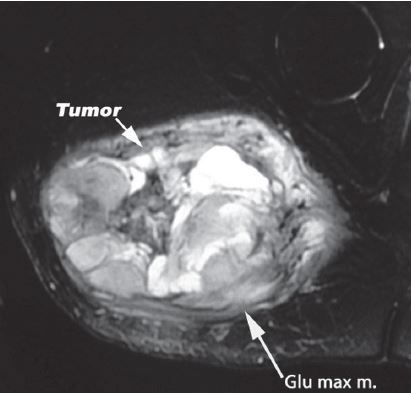

Excision of Benign Soft Tissue Tumors

Buttockectomy